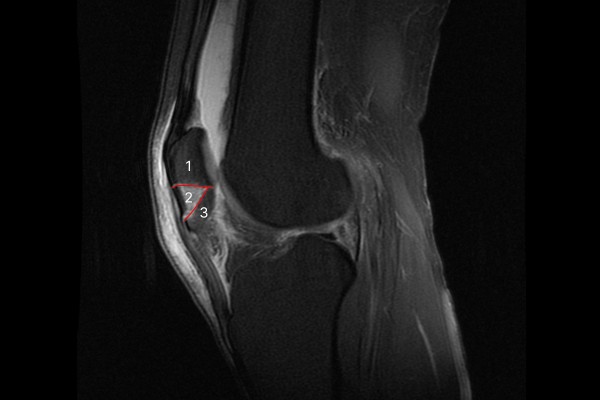

MRI 촬영 결과를 보면 2개의 골절선으로 인하여 슬개골이 3조각으로 나뉜 것이 확인됩니다.

9f695db682e5f1ea0b431dfdec73e7ff_1766564253_1803.jpg

측면에서 확인해봐도 동일하며 우측 무릎뼈 (슬개골) 골절(Fx. patella knee Rt.3)으로 진단하였습니다.